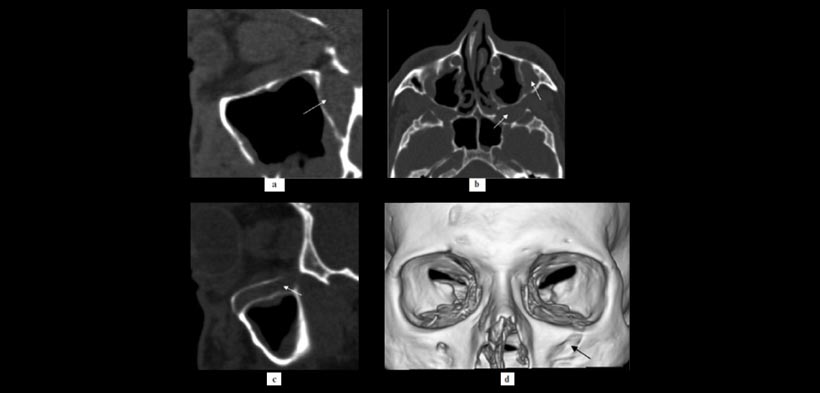

Figura 2. El remodelado óseo: TC sagital muestran efectos de la remodelación ósea en la fosa pterigopalatina (a, flecha) y el canal infraorbitario (c, flecha) de la parte izquierda. Las mismas estructuras se muestran en el plano axial (B, flechas). Reconstrucción computarizada tridimensional muestra la ampliación del foramen infraorbitario del lado izquierdo (d, flecha).